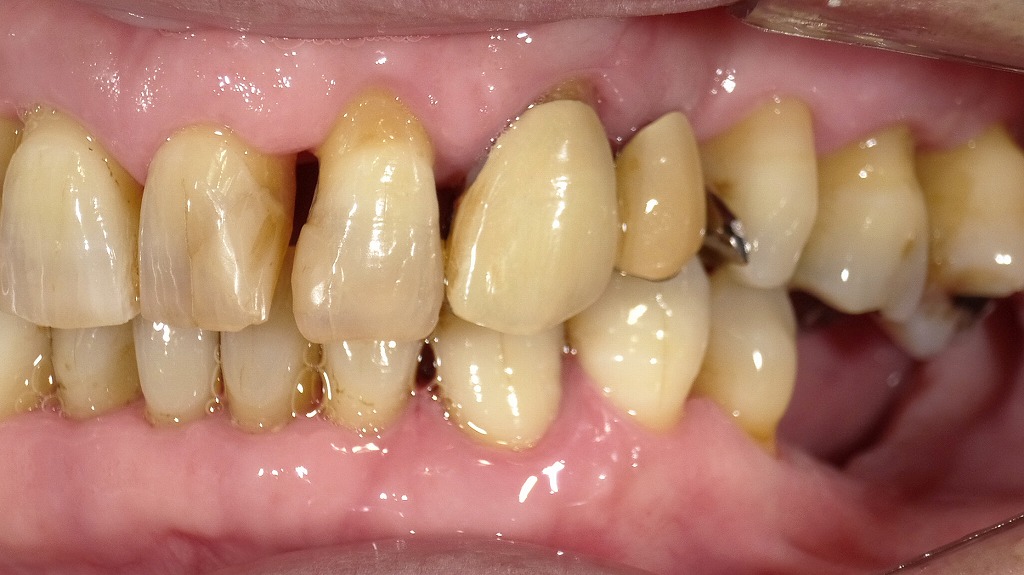

■ 感染する歯周病、予防できる歯ぐきへ。ケア後の実例

① プラークコントロールが良好になっている

- 歯頚部(歯と歯ぐきの境目)の黄白色のプラークがほとんど見られません。

- 表面が比較的クリアで、前回の状態と比べて自宅でのブラッシング精度が向上していると考えられます。

② 歯石除去後の状態

- 黒色・褐色の縁下歯石や縁上歯石が明らかに減少しています。

- 下顎前歯部・臼歯部ともに、歯面が滑沢になっており、スケーリング/ルートプレーニングが行われた後の典型的な状態です。

③ 歯ぐきが下がっている(歯肉退縮)

- 歯根の一部が露出しており、歯肉退縮が確認できます。

- これは以下の要因が関与することが多いです:

- 長期的な歯周病による歯周組織破壊

- 歯石除去後、腫れが引いたことで歯肉ラインが本来の位置へ戻る

- 見た目は「歯が伸びた」と感じる場合がありますが、炎症改善のプロセスでよく見られます。

④ 歯肉の炎症が改善している

- 歯肉が赤く腫れぼったかった前回に比べ、今回はピンク色に近づき、引き締まった形態になっています。

- 歯間乳頭の丸みが減り、シャープな形態に戻ってきているのが特徴です。

- 出血しやすい状態は改善していると推測されます。

■ 総合評価

今回の画像は、歯周基本治療が奏功し、炎症が軽減して健康的な歯肉に改善している過程を示しています。

- プラークコントロール良好

- 歯石除去後の滑らかな歯面

- 炎症が取れて歯肉が引き締まる

→結果として歯肉退縮が見えやすい

これは歯周治療が正しく進んでいるサインです。この様に治療と毎日のケアで歯ぐきの炎症が改善すると、口腔内の細菌量が減り、歯周病の“感染リスク”を大きく下げることができます。

■ 今後必要なケア

- 引き続き丁寧なブラッシング(特に歯頚部)

- フロス・歯間ブラシの併用

- 定期的なメインテナンス(1〜3ヶ月)

- 知覚過敏が出た場合は、コーティング材や知覚過敏抑制剤の検討